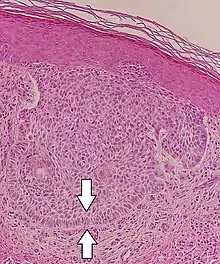

Superficial basal-cell carcinoma (also known as "superficial multicentric basal-cell carcinoma") | Occurs most commonly on the trunk and appears as an erythematous patch.[28]: 748 [29]: 647 | ![]() | |